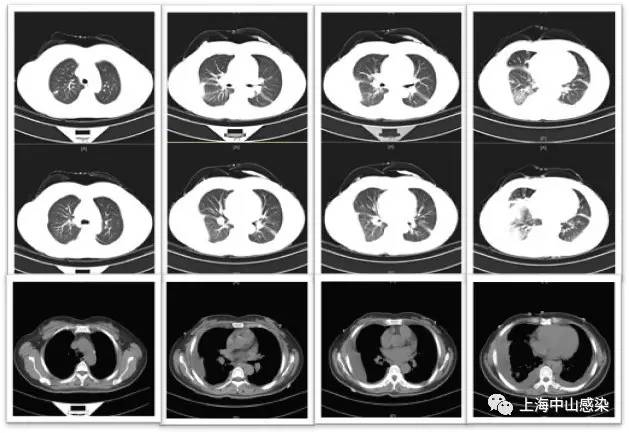

肺吸虫血清抗体阳性,诊为肺吸虫病,吡 喹酮1g(200mg*5片),tid,3天,8.29 CT3复查病灶明显吸收。

2.本例有意思的地方是有不符合常见寄生虫病的特点:血嗜酸性粒细胞不高;血IgE正常;胸腔积液无嗜酸性粒细胞;肺内未见虫体移行性空洞或囊性病灶;但也有多处提示:多浆膜腔积液;抗菌治疗无效;肺内病灶呈游走性;患者喜食醉蟹。

CT3.jpg